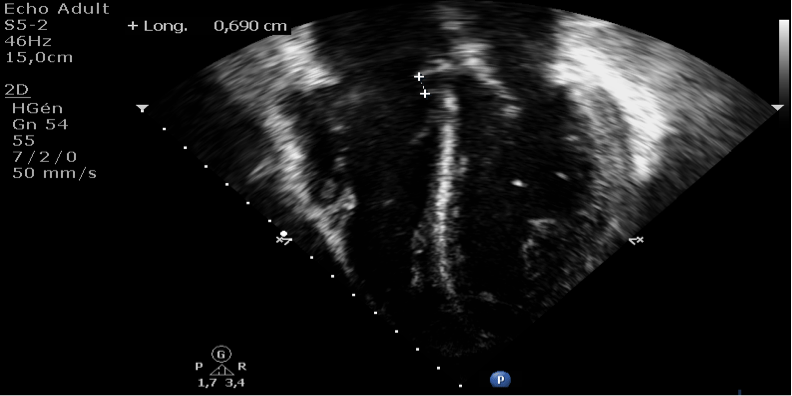

Cela entraîne une difficulté à respirer. Le médecin procédera ensuite à un examen clinique, une radiographie du thorax ou une échocardiographie lui donnant une image du cœur. Un produit opaque aux rayons x est alors directement injecté au niveau du ventricule gauche et des radiographies sont effectuées. On distingue insuffisance cardiaque droite et insuffisance cardiaque gauche. Masculin ce qui rejoint les données de la littérature.

La radiographie thoracique de face montre un cœur augmenté de volume ; Le médecin procédera ensuite à un examen clinique, une radiographie du thorax ou une échocardiographie lui donnant une image du cœur. L'insuffisance cardiaque gauche (insuffisance ventriculaire gauche ivg). L'insuffisance ventriculaire gauche se produit lorsqu'il y a un dysfonctionnement du ventricule gauche provoquant un apport insuffisant de sang aux organes vitaux du corps. Ic droite (ne concernant que le ventricule droit) ou gauche (ne concernant que le ventricule gauche)